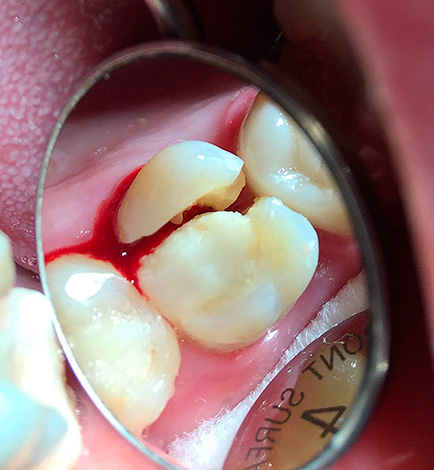

Dal punto di vista di un dentista, la situazione in cui un paziente cammina per anni con un dente cariato, distrutto alla base, appare come segue: questa persona non si dispiace per se stessa. Il fatto è che in questi casi, le radici dei denti devono essere rimosse urgentemente (vedi l'esempio nella foto sotto).

Il motivo è semplice: le radici marce sono un focolaio di infezione e più sono in bocca, più i problemi sono pronunciati e sono tutt'altro che limitati a alitosi costante. Questi "marci" porosi come un aspirapolvere assorbono da soli batteri e particelle di cibo. Oltre al cibo in decomposizione, sui residui dei denti sono presenti anche placca difficile da rimuovere e quasi sempre tartaro sopra e sottogengivale, che causa sofferenza alle gengive.

In quasi il 100% di tali casi, si osserva un processo infiammatorio in cima alle radici marce, accompagnato da rarefazione del tessuto osseo, si forma un granuloma o una cisti. In poche parole, nella parte superiore della radice c'è un sacco purulento, che sta solo aspettando che le ali si spezzino con la formazione di un "flusso".

La foto sotto mostra un esempio di denti estratti con cisti alle radici:

Le fotografie seguenti mostrano l'estrazione del dente, la cui parte della corona viene distrutta quasi al livello delle gengive: